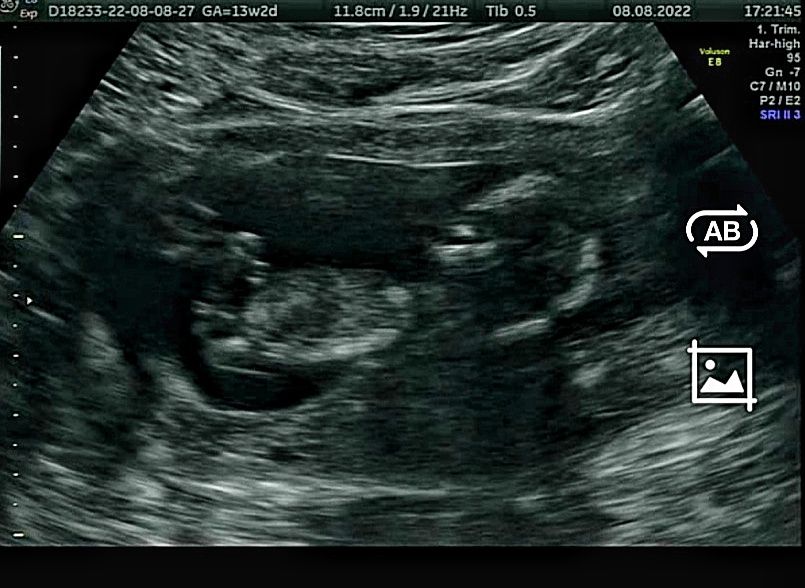

УЗИ, КТГ, доплерВчем привет! На днях была на первом скрининге беременности в 13.2н и арач уже предположила пол😊 она как-то очень уверенно сказала 😂

По мнению врача у нас девочка😍

А вы кого видите?) смотрела в интернете, что по наклону бугорка определяют)